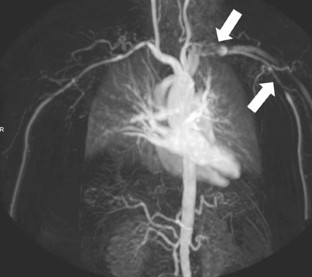

Diese Übersicht fasst die Möglichkeiten und Limitierungen der Magnetresonanztomographie (MRT) und Magnetresonanzangiographie (MRA) zur Diagnostik der Großgefäßvaskulitiden zusammen. Dank der detaillierten Darstellung des Lumens und der Wand großer und mittelgroßer Arterien und der typischerweise kräftigen, muralen Kontrastmittelaufnahme vaskulitischer Prozesse sind die MRT und MRA besonders für die Diagnostik der Großgefäßvaskulitiden geeignet. Das kranielle, intrakranielle und extrakranielle Verteilungsmuster kann in einer kombinierten Untersuchung der thorakalen Aorta mit ihren supraaortalen Ästen und der hochauflösenden Darstellung der oberflächlichen Kopfarterien bestimmt werden. Typische Sequenzprotokolle für die monophasische und die zeitaufgelöste MRA bei 3 T werden exemplarisch aufgeführt. Die MR-Bildgebung hat das Potenzial, die Gefäßsegmente mit den stärksten Entzündungszeichen für die Biopsie zu bestimmen und die Erfolge der Therapie zu kontrollieren. Die ersten Ergebnisse multizentrischer Studien zum Stellenwert dieser neuen Verfahren werden in den nächsten Jahren erwartet. Zur Beurteilung einer ZNS-Vaskulitis stellt die MRA ein interessantes, nichtinvasives Verfahren dar, das insbesondere bei pathologischem Befund die invasive Katheterangiographie ersetzen kann.

The potentials and pitfalls of magnetic resonance imaging (MRI) and magnetic resonance angiography (MRA) in the diagnosis of large vessel vasculitis are summarized in this review article. With the ability to visualize the lumen and vessel walls of large and medium sized arteries, MRI and MRA have great potential to play a unique role in the diagnosis of large vessel vasculitis. This is underlined by the fact that mural inflammatory changes typically involve uptake of contrast agent that can be visualized with MRI. The cranial, intracranial and extracranial involvement pattern can be studied in a combined approach including an MRI examination of the superficial cranial arteries and an MRA examination of the thoracic aorta with its major supra-aortic branches. Typical MRI sequence parameters are given including monophasic MRA and time-resolved MRA protocols at 3 T. The MRI and MRA techniques have the potential to determine the most suitable (inflamed) segment for temporal artery biopsy and to monitor treatment. Initial results of multicenter studies for the diagnostic accuracy of these relatively new methods are expected soon. The MRA technique is recognized as an interesting alternative to invasive catheter angiography for the evaluation of central nervous system (CNS) vasculitis.